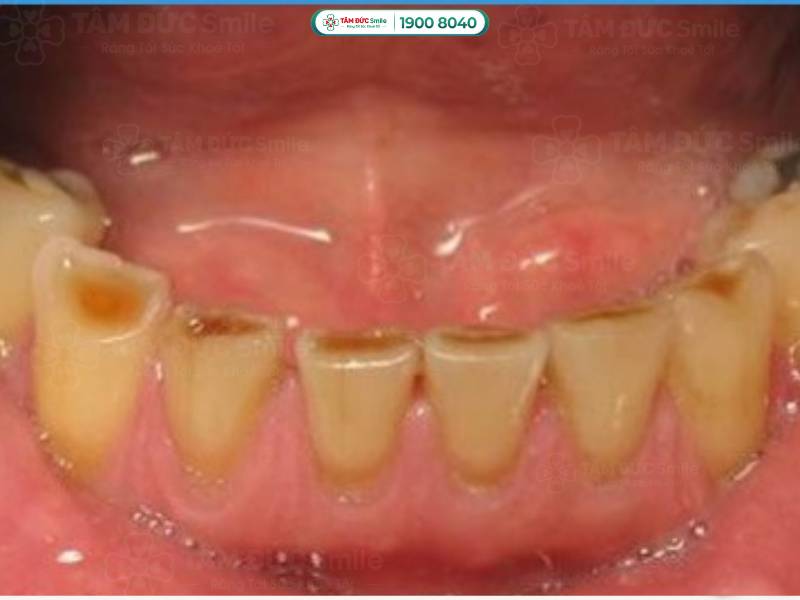

Răng bị mòn mặt nhai là hiện tượng lớp men răng ở phần trên cùng của răng bị bào mòn. Trên mặt nhai xuất hiện các vết lõm nông hoặc sâu không đồng đều, làm mất thẩm mỹ và ảnh hưởng chức năng răng miệng.

Răng bị mòn mặt nhai do mất mô răng. Lớp men răng bảo vệ không còn, cấu trúc của bề mặt nhai có sự thay đổi, bắt đầu xuất hiện các vết lõm. Tùy vào mức độ mòn men răng, vết lõm có thể nông hoặc sâu, làm bạn cảm thấy ê buốt khi ăn nhai.

Mặt nhai của răng bị mòn được chia thành 3 cấp độ từ nhẹ đến nặng:

- Mức độ nhẹ: Chỉ lớp men răng bị mòn, khi ăn đồ nóng hay lạnh, bạn sẽ cảm thấy hơi ê buốt.

- Mức độ nặng: Không chỉ lớp men răng, ngà răng bên trong cũng bị phá hủy. Bạn cảm thấy ê buốt thường xuyên, kèm theo cơn đau nhức ở vị trí răng bị mòn.

- Mức độ cực kỳ nghiêm trọng: Răng yếu, xuất hiện tình trạng lung lay, đổi màu. Nếu bạn không điều trị kịp thời, tủy răng ở sâu bên trong cũng bị ảnh hưởng.

Răng bị mòn mặt nhai là hiện tượng lớp men răng ở phần trên cùng của răng bị bào mòn

Lớp men răng bị mất làm cho răng chuyển dần thành màu vàng nâu, rất mất thẩm mỹ. Ngoài ra, răng mất lớp men bảo vệ sẽ ngắn hơn các răng khác. Nếu tình trạng này xuất hiện ở răng cửa, thẩm mỹ nụ cười của bạn sẽ bị ảnh hưởng.